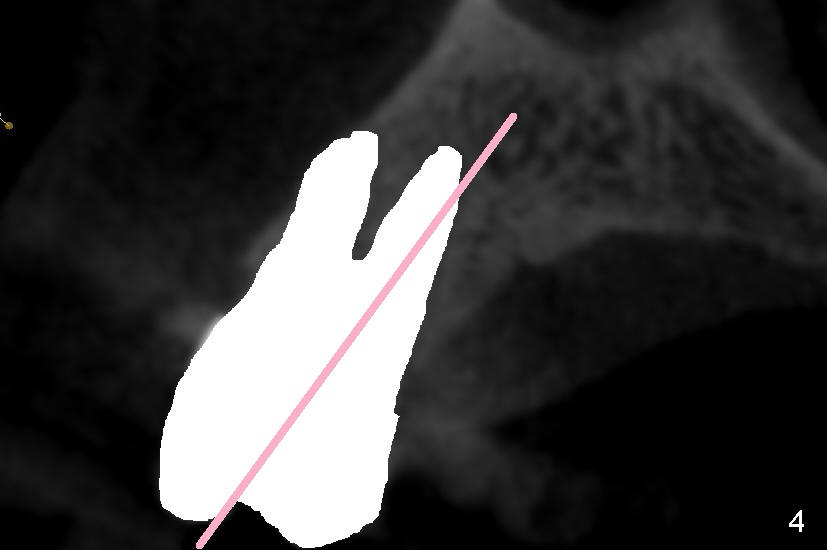

Even in a single root socket, osteotomy is to be created in the palatal wall. To get a "catch", a drill or osteotome (RT for example; Fig.3 pink line) is placed more or less perpendicular to the palatal wall. Once the catch is achieved, the axis of osteotomy is changed (Fig.3 curved arrow), more or less parallel to the bone morphology (buccal and/or palatal walls, Fig.4). Gradually the osteotomy is increased in diameter (Fig.5 pink area). In the single root, a separate, palatal socket has been created with formation of a septum. Subsequently, taps and the implant (tapered, Fig.6 red portion) will push the existing or just formed septum buccally (from yellow area to grey area). The fractured and displaced septum is going to participate in repairing the buccal apical defect if the pre-existing infection is under control under protocol proposed by Tatum group.